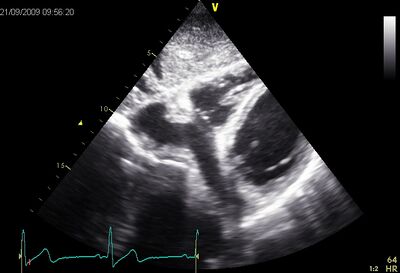

A persistent left superior vena cava is the most common variation of the thoracic venous system. A VCSSP comes in 0.3% of the population. In one VCSSP, the left brachiocephalic vein is not fully developed, and the left upper extremity, the head and neck have their drain into the right atrium via the coronary sinus, with the result that the coronary sinus to dilate by volume overloads.

| Coronary sinus dilation (Plax) | Coronary sinus with contrast (Plax) |

| Dilated coronary sinus on AP4CH | Dilated coronary sinus subcostal |